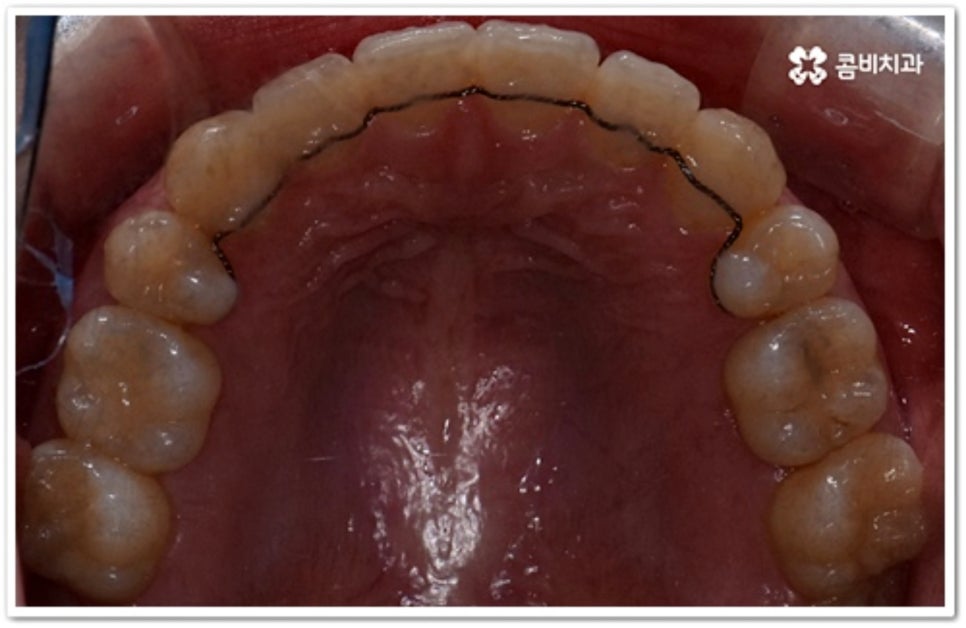

치아는 제자리로 돌아가려는 성질을 가지고 있어서 덧니 발치 교정이 끝난 후 일정 기간 동안은 유지 장치를 착용하여 이를 예방하고 정기 검진을 꼬박꼬박 받으면서 사후 관리를 철저하게 해 주는 게 좋을 거예요. 유지장치에는 고정식과 가철식이 있는데 치아 안쪽에 얇은 철사를 붙이는 고정식 (사진에서 볼 수 있는 사례) 은 앞니가 틀어지는 것을 방지해 주고, 뺐다 꼈다 하는 가철식은 교정 치료할 때 악궁 확장을 한 경우 전체 치열을 유지하기 위해 필요한 방식이라고 할 수 있어요. 환자분들 각각의 치료 과정이나 구강 상태에 따라 둘 중 하나를 선택하거나 두 가지 다 해야 하는 경우가 생길 수 있습니다.